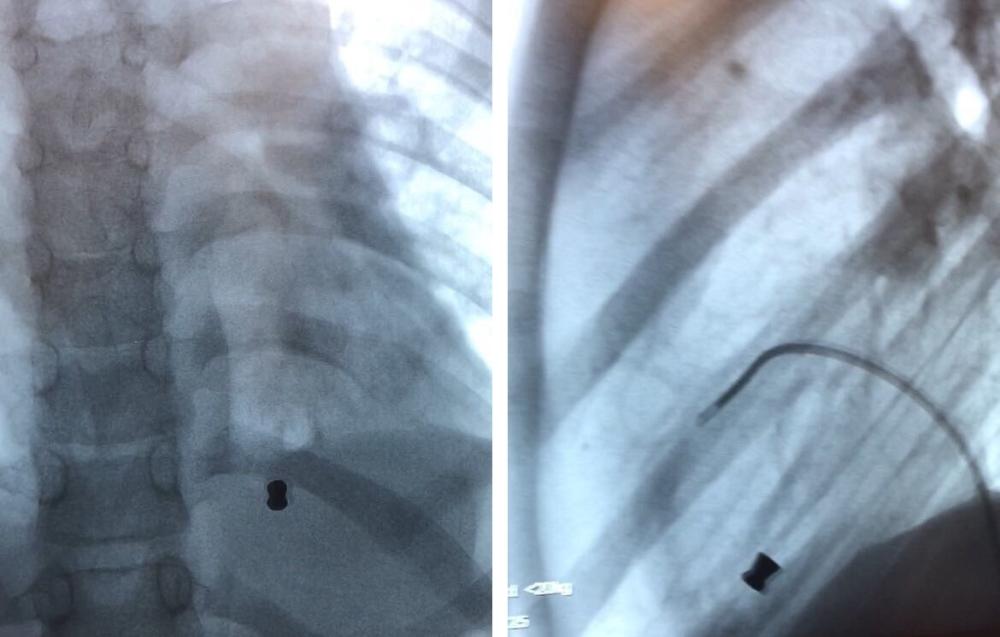

الأشعة توضح موضع الرصاصة. (عكاظ)

وذكر استشاري أمراض القلب والقسطرة الدكتور عبدالله القويعي أن مركز القلب استقبل طفلاً يبلغ من العمر 11 عاماً، بعد إصابته برصاصة بندقية هوائية أثناء عبثه بها، إذ اخترقت القفص الصدري واستقرت في الجهة اليمنى من القلب، مضيفاً أن حالة الطفل من الحالات النادرة الحدوث، وتم على الفور تنويمه في العناية المركزة القلبية، والتأكد من استقرار حالته الصحية، ثم تحويله لمعمل القسطرة، وبفضل من الله تم استخراجها من القلب.